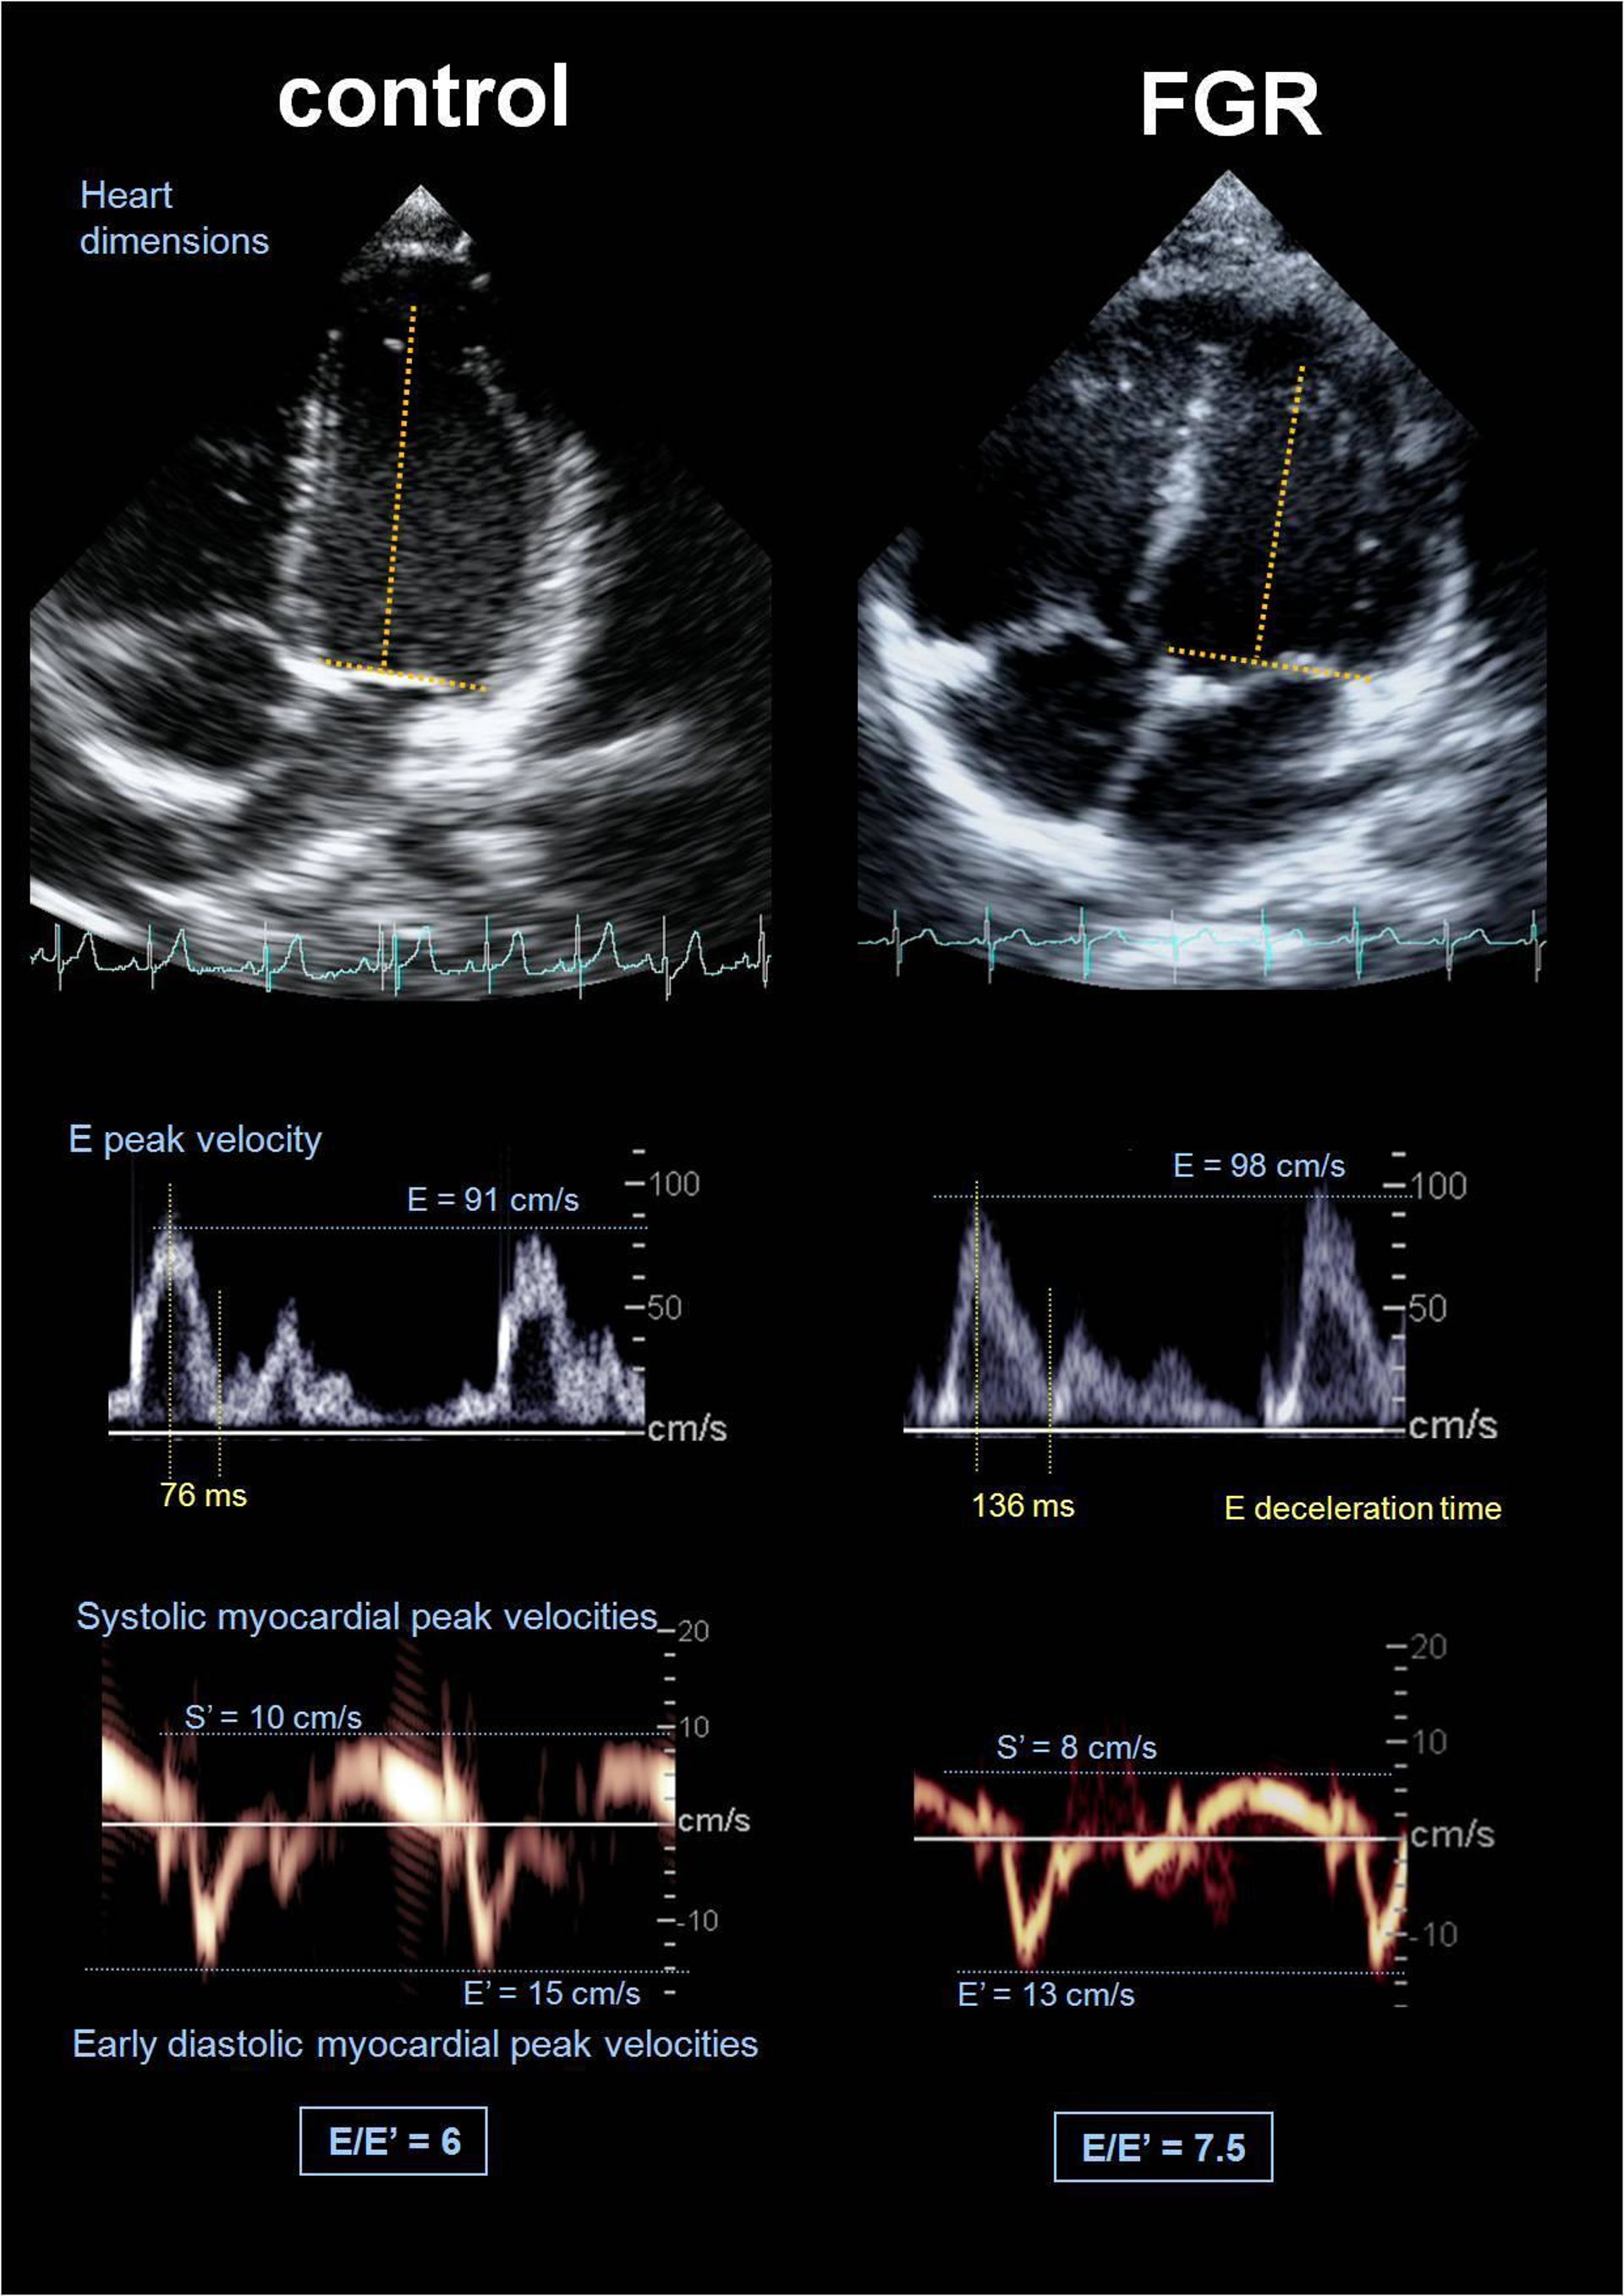

El estudio evaluó a 200 niños, 80 de los cuales sufrían un retraso en el crecimiento, y a través de una radiografía constató que en éstos últimos la forma del corazón era más redonda, la del grupo de control era más alargada; su tensión arterial era más alta, aunque todavía no requerían medicación, y presentaban un mayor grosor de las arterias carótidas.

La gravedad de la alteración es distinta en función de la falta de nutrientes y oxígeno que haya sufrido en el útero el bebé --se desconocen los motivos--, que para sobrevivir obliga al corazón a adaptarse y, fruto de la dilatación, ensancharse.

Se trata de un cambio adaptativo a nivel fisiológico que también "tiene un precio" a nivel funcional porque las "fibras cardíacas --de estos niños-- se mueven a una velocidad inferior", advirtió Gratacós, que señaló que las consecuencias pueden ser visibles generalmente más allá de los 40 años.